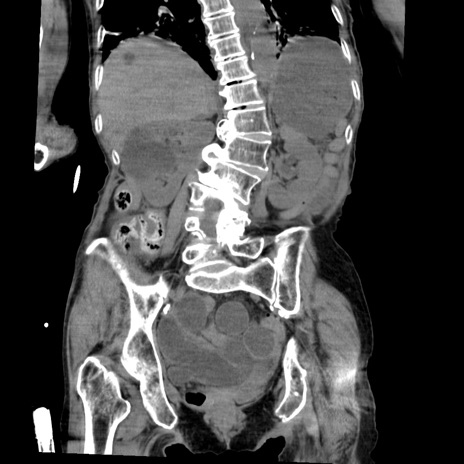

症例27(冠状断像)

【症例】80歳代女性

【主訴】嘔吐、腹痛

【現病歴】数時間前より嘔吐あり。心窩部痛出現し、徐々に右下腹痛あり。その後も数回嘔吐あり救急搬送となる。

【既往歴】左大腿骨頚部骨折手術

【身体所見】腹部は膨隆しているが軟らかく圧痛なし。腸雑音はやや亢進。

【データ】WBC 12000、CRP 19.05